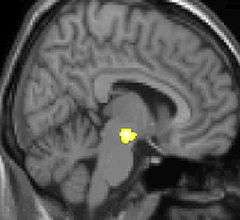

Voxel-based morphometry (VBM) is a neuroimaging analysis technique that allows investigation of focal differences in brain anatomy, using the statistical approach of statistical parametric mapping.

In traditional morphometry, volume of the whole brain or its subparts is measured by drawing regions of interest (ROIs) on images from brain scanning and calculating the volume enclosed. However, this is time consuming and can only provide measures of rather large areas. Smaller differences in volume may be overlooked. VBM registers every brain to a template, which gets rid of most of the large differences in brain anatomy among people. Then the brain images are smoothed so that each voxel represents the average of itself and its neighbors. Finally, the image volume is compared across brains at every voxel.

One of the first VBM studies and one that came to attention in mainstream media was a study on the hippocampus brain structure of London taxicab drivers.[4] The VBM analysis showed the back part of the posterior hippocampus was on average larger in the taxi drivers compared to control subjects while the anterior hippocampus was smaller. London taxi drivers need good spatial navigational skills and scientists have usually associated hippocampus with this particular skill.